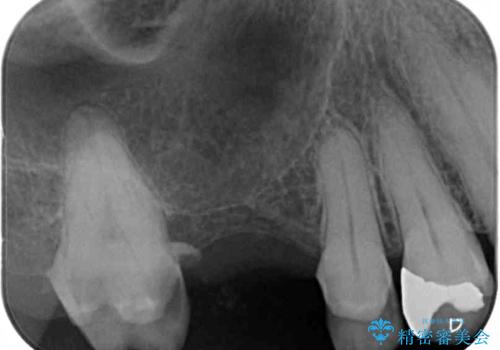

- 詰め物が外れたまま放置してしまったとのことで来院された患者様です。

詰め物が外れた部分は虫歯が進行しており、周辺には歯石が付着している状態でした。

虫歯が大きく進行していましたが、歯髄(神経組織)にまで及ぶものではなかったため、無事に虫歯治療を行うことができました。